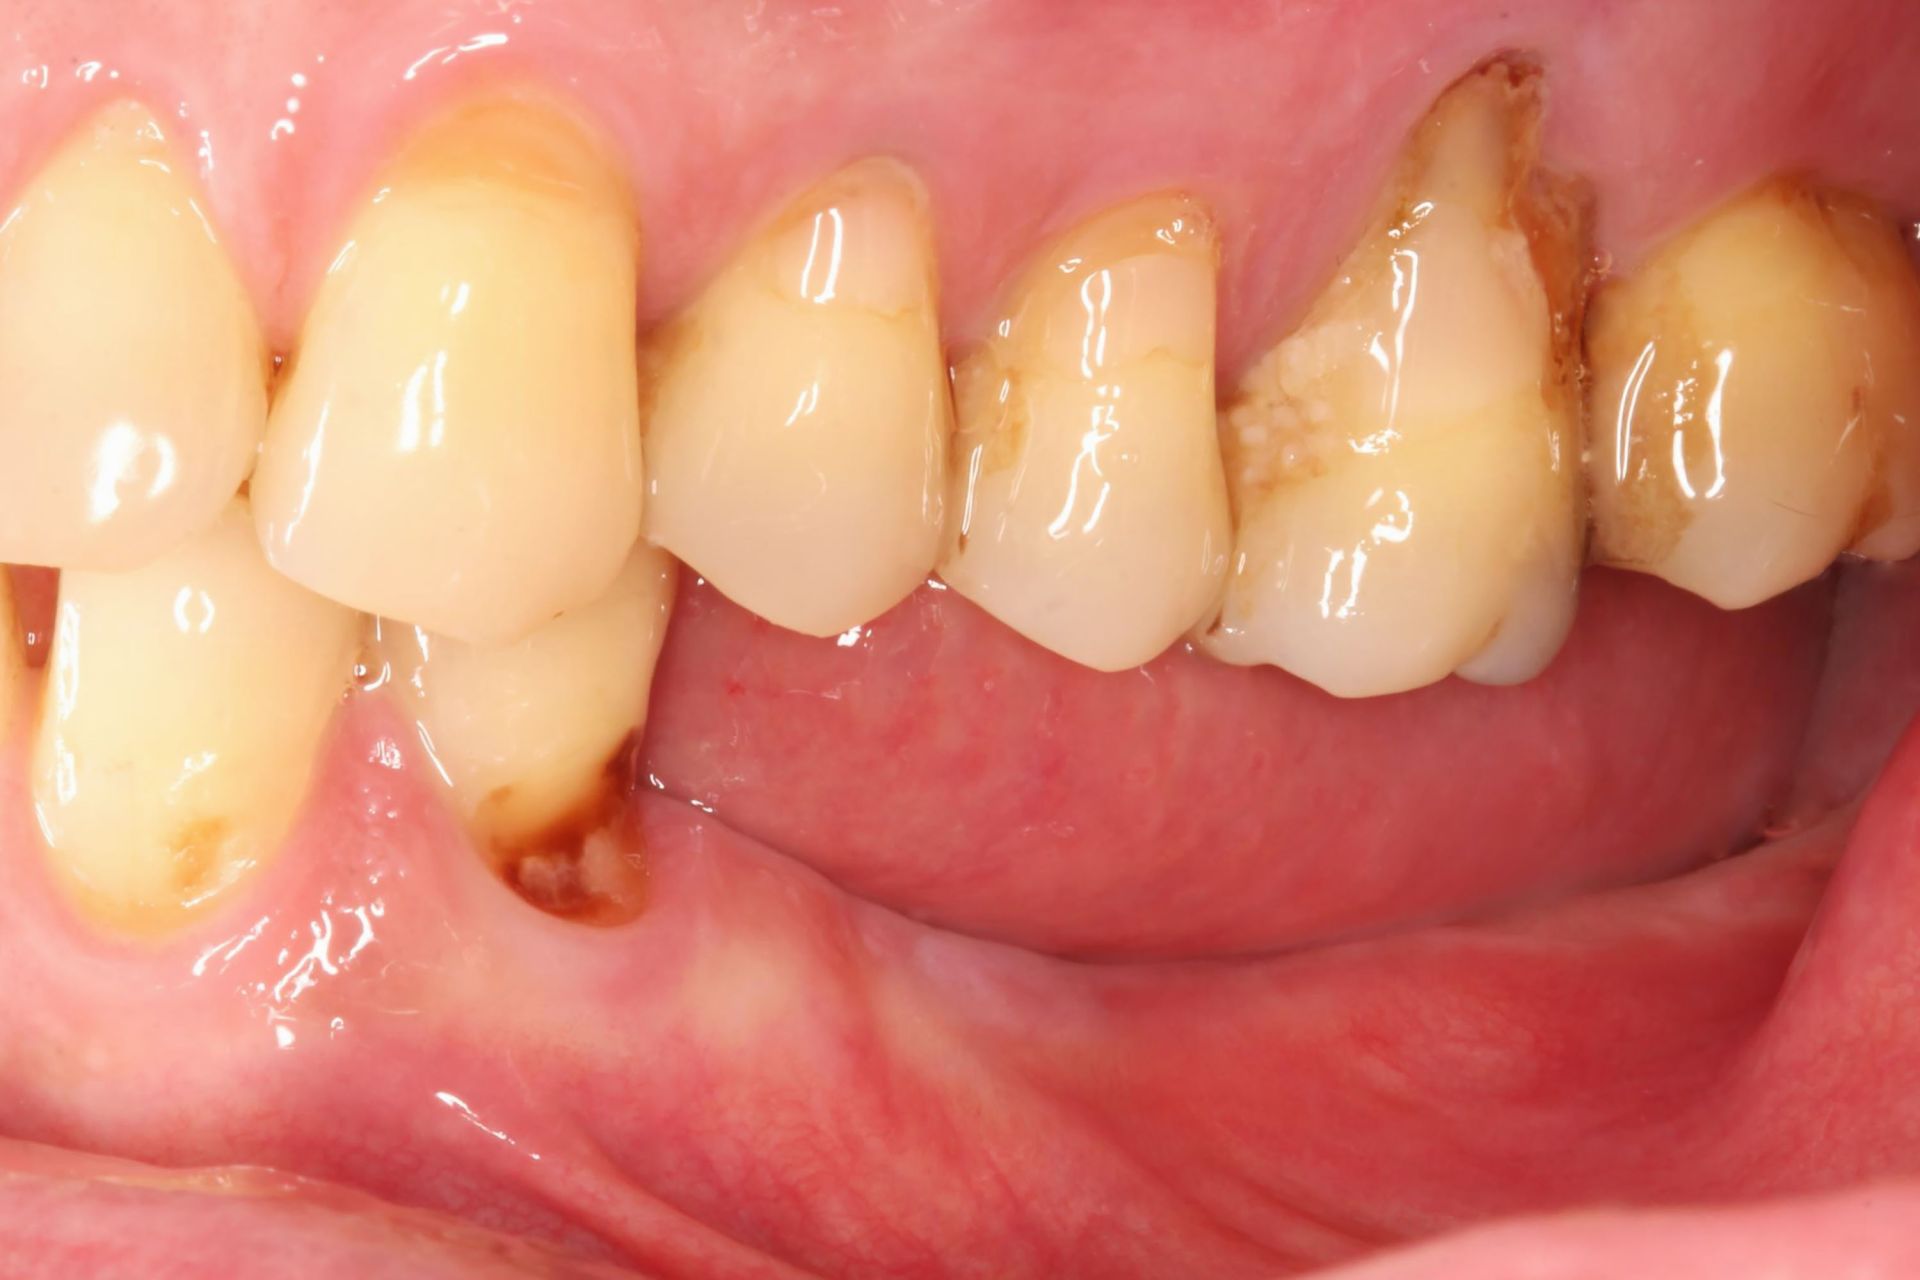

今天想跟分享一個非常典型的重建案例。患者是一位 50 歲的韓先生,正值壯年,本該是享受美食與生活的年紀。但他初次來到診所時,神情其實是相當困擾的。經過我們詳細的口內檢查,發現他左下顎的後牙區有大範圍的缺牙,這導致他長期以來面臨一個很嚴重的問題——「嚴重依賴單邊咀嚼」。

韓先生在諮詢時跟我提到,這種情況已經持續很長一段時間了。他在主述中很生動地形容:「以前稍微硬一點的東西,我想都不敢想。」這句話聽在我們牙醫師耳裡,其實是很心疼的。因為牙齒的功能不僅是美觀,更重要的是「咀嚼效率」。當失去了大臼齒的研磨功能,面對纖維較粗的蔬菜或是口感較硬的肉類,患者往往會產生畏懼心理,甚至直接放棄攝取這類食物,長久下來會導致營養攝取的不均衡。

針對韓先生的狀況,我們的治療目標非常明確:必須恢復他左側的咀嚼功能,平衡雙側咬合。經過 3D 電腦斷層掃描(CBCT)的骨質評估後,我們制定了植牙治療計畫,鎖定的位置是左下顎的三顆關鍵牙齒:分別是「左下第二小臼齒」、「左下第一大臼齒」以及「左下第二大臼齒」。